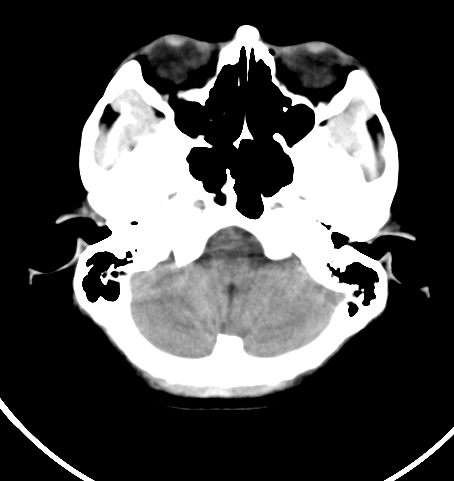

病人女 35岁 自述头晕 头痛

双侧基底节区及右侧丘脑区多发点状钙化,周围未见水肿及占位征象.余未见明显异常.考虑:脑囊虫病<囊虫的退变或死亡期>请结合有无相关病史.

颅内有散在钙化